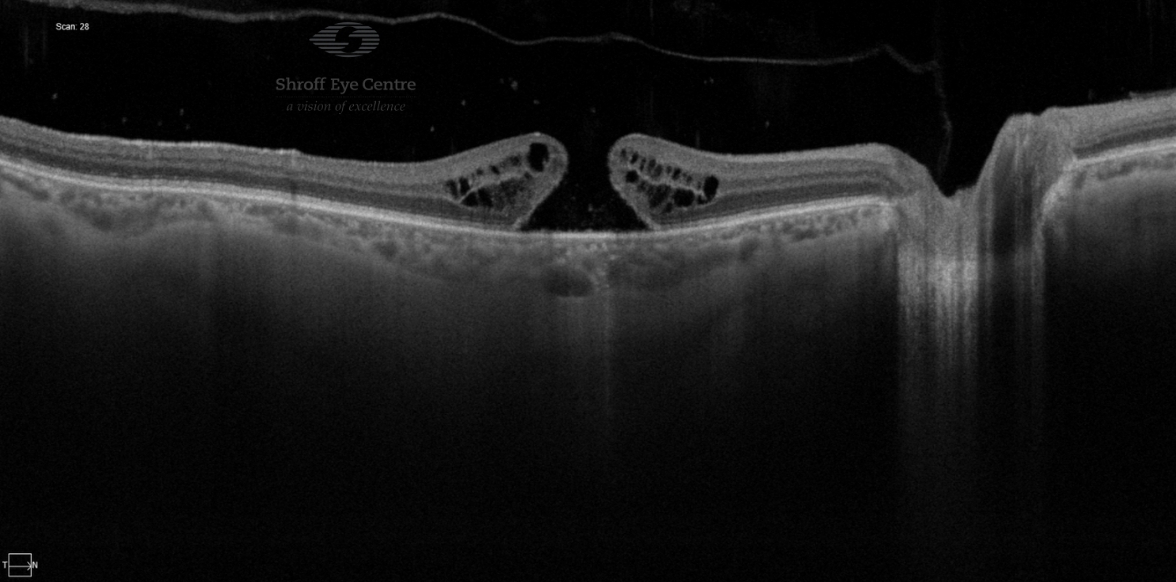

- OCT (optical coherence tomography) is a non-invasive scan of the retina which confirms the diagnosis. OCT takes cross-sectional images of the retinal layers and helps in ruling out other similar-looking diseases of the eye. It also helps to pick up any early changes in the fellow eye.

In 2013, the International Vitreomacular Traction Study Group also formed a classification scheme of vitreomacular traction and macular holes based on OCT findings (1,3)

- Vitreomacular adhesion: No distortion of the foveal contour; size of attachment area between hyaloid and retina defined as focal if ≤1500 microns and broad if >1500 microns

- Vitreomacular traction (VMT): Distortion of foveal contour present or there are intraretinal structural changes in the absence of a full-thickness MH; size of attachment area between hyaloid and retina defined as focal if ≤1500 microns and broad if >1500 microns

- Full-thickness macular hole (FTMH): Full-thickness defect from the internal limiting membrane (ILM) to the retinal pigment epithelium. Size is based on the horizontal diameter at the narrowest point: small (≤250 μm); medium (250–400 μm); or large (>400 μm). The cause may be primary or secondary, and VMT may be present or absent